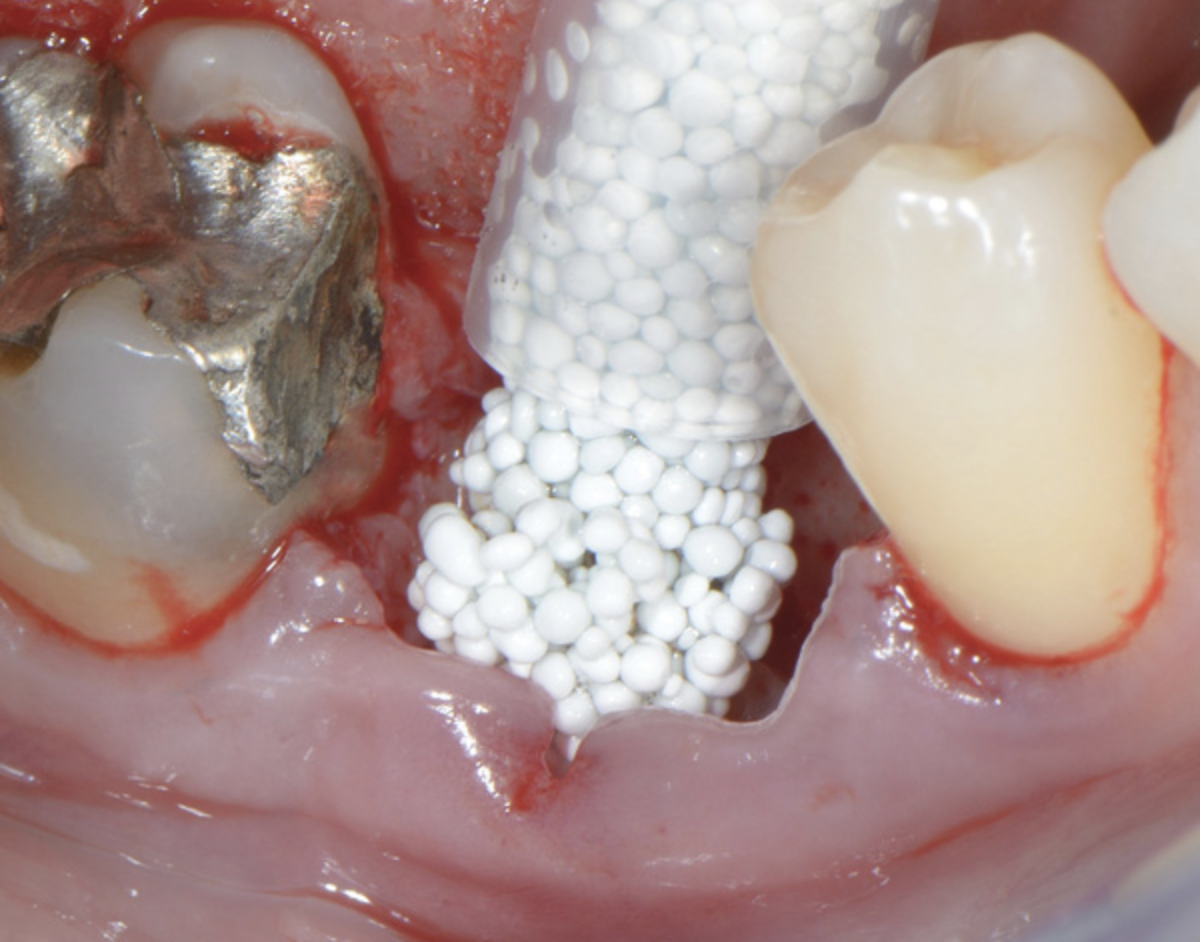

Fig 7. Insertion of the PLGA-TCP self-setting composite graft material in the extraction socket.

Figure 7

Figure 7 demonstrates the handling of the material as it is inserted into a large, mandibular molar extraction socket. The graft was covered with a collagen barrier, but no primary closure was either planned or obtained. The area healed uneventfully and was reentered with a flap procedure at 8 months for implant placement (Figure 8). Based on Figure 8 it is evident that much of the graft material had resorbed and was replaced with vital bone while the width of the alveolar ridge was preserved to facilitate ideal placement of an endosseous dental implant.

A new form of tricalcium phosphate has been developed for ease of use in a syringe system, which sets the material in the grafted site. The system is made up of one syringe containing 99% ß-TCP granules coated with poly(lactide-co-glycolide) (PLGA). This is mixed with an ampule containing BioLinker® (N-methyl-2-pyrrolidone and water) (GUIDOR® easy-graft®, Sunstar, www.GUIDOR.com) (Figure 7). A study demonstrated the biocompatibility and resorption of this material in extraction sockets.8 With its ability to resorb slowly and fully and to maintain its shape during healing, GUIDOR easy-graft is potentially an ideal bone replacement graft for defects of varying sizes, either with or without a barrier.